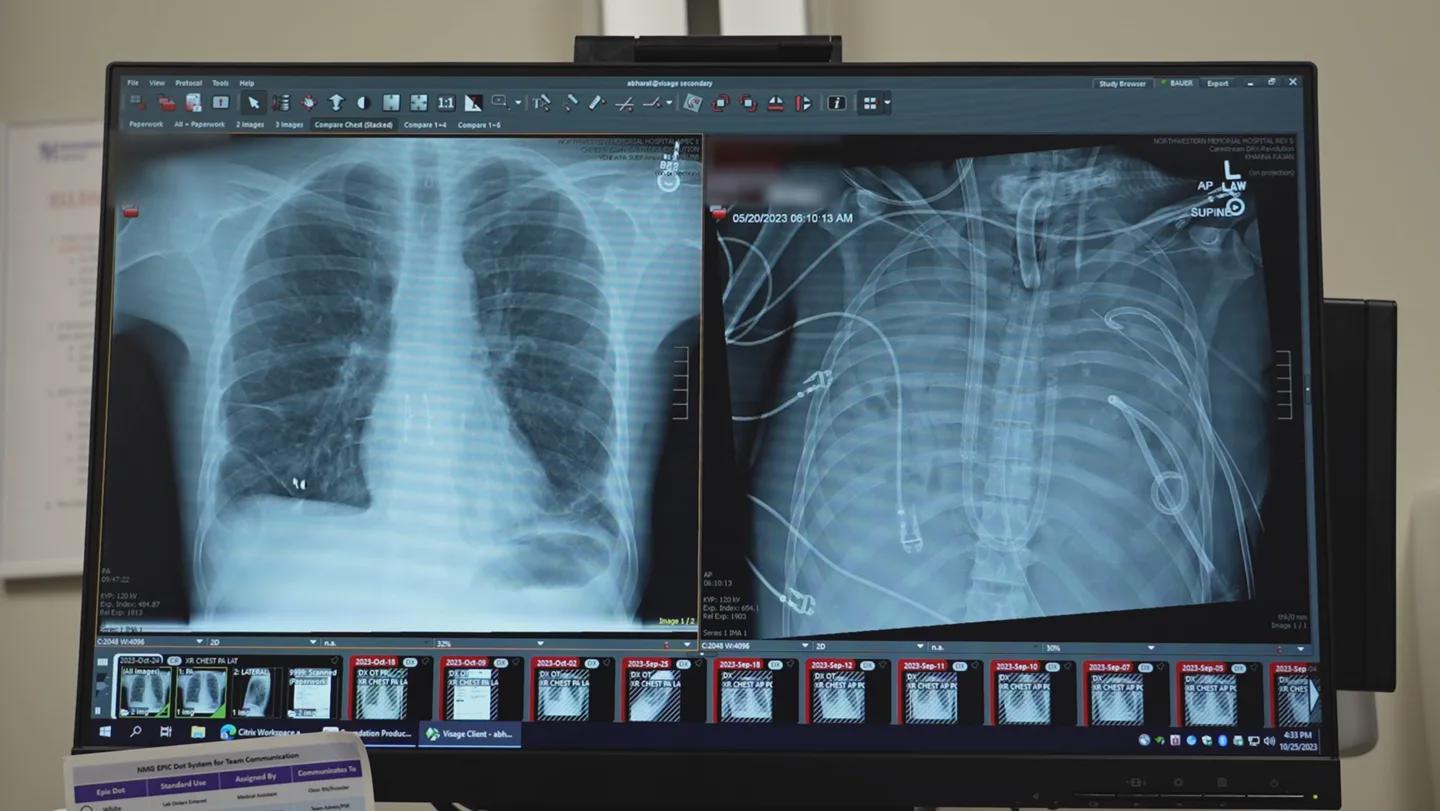

>Surgeons removed a man’s irreparably damaged lungs and kept him alive for 48 hours with artificial lungs until he could get a transplant.

>Doctors crafted shunts, tubes and pumps into a system that oxygenated blood and supported blood flow through the heart, the team reports January 29 in *Med.* It is proof that [a true artificial lung](https://www.cell.com/med/fulltext/S2666-6340(25)00412-X) can keep a patient alive until donor organs are available, says Ankit Bharat, chief of thoracic surgery at Northwestern University Feinberg School of Medicine in Chicago.

>In 2023, a 33-year-old man from St. Louis caught influenza B and his lungs began to deteriorate. He was hospitalized and got a second infection with *Pseudomonas aeruginosa* bacteria that were resistant to antibiotics. The infection spread to his blood. The dual infections and damage from overzealous immune reactions caused his lungs to fail.